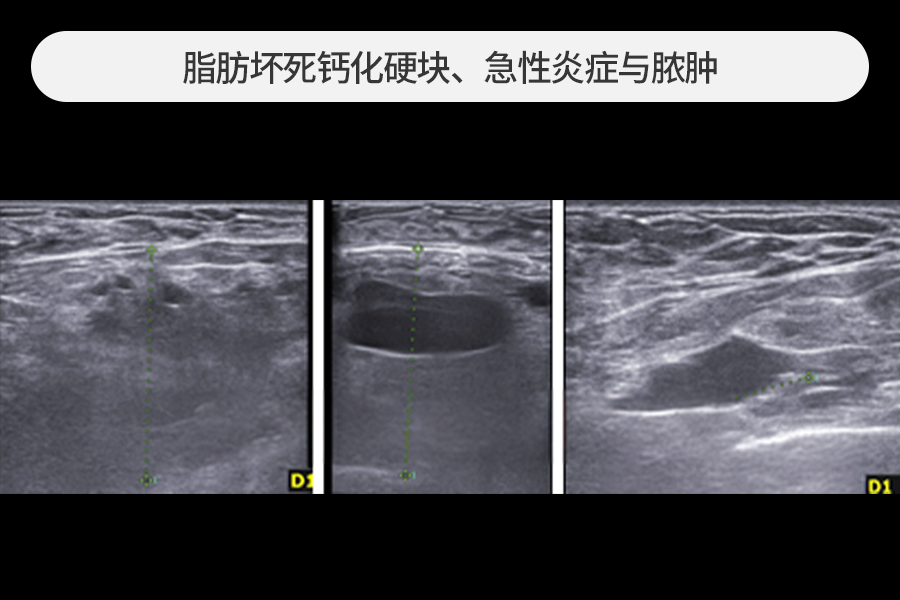

4~5cm 大小的脂肪移植硬块去除

该患者因胸部脂肪移植后摸到乳房硬块而来院,观察到4~5cm大小的巨大钙化硬块。

尺寸较大的脂肪移植硬块发生急性炎症时风险较高,需要尽快去除。

在超声引导下保留正常组织,仅安全去除了硬块。

去除乳房内积聚的脓肿

该患者胸部脂肪移植后发生严重急性炎症,乳房内部已形成巨大脓肿(脓袋)。

这种情况相比普通的脂肪移植副作用治疗切口更大,可能需要放置引流管约1~2周。